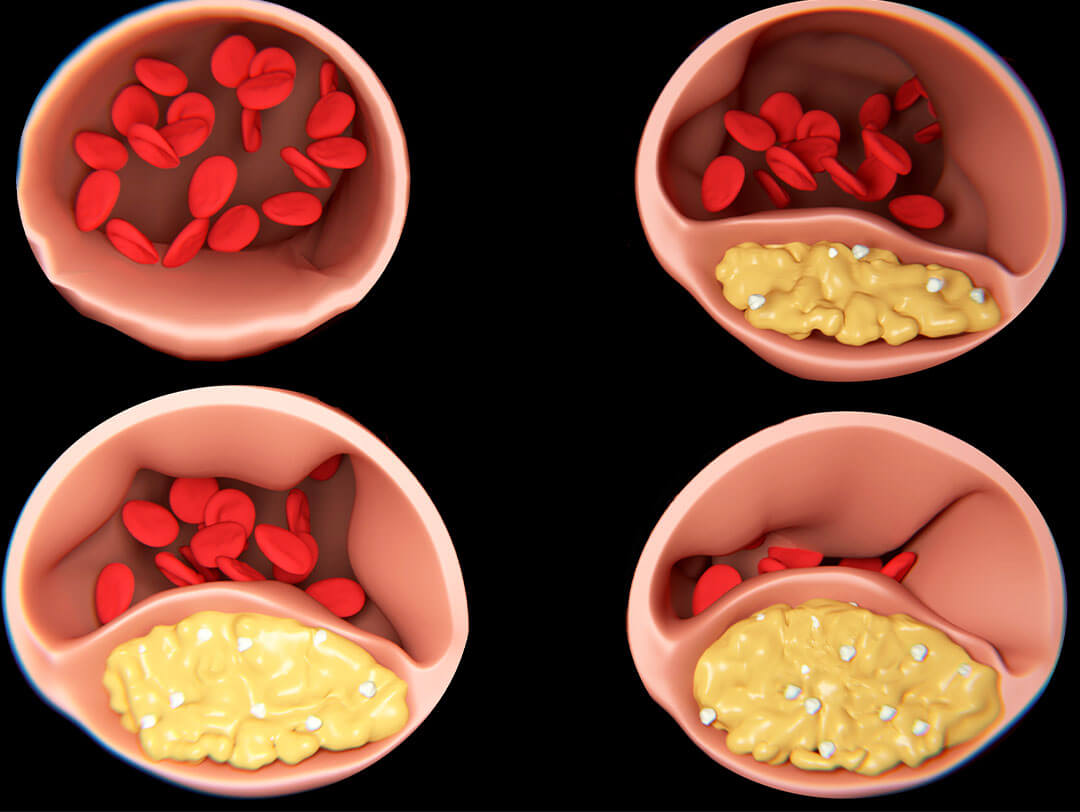

One of the main causes of the waste barrier is the poorer blood circulation that occurs during menopause.

Levels of oestrogen - the main female sex hormone - rapidly drop during this period and plays a central role in this.

Oestrogen keeps blood vessels elastic:

Normally, oestrogen keeps your blood vessels supple and blood flowing freely.

When this support is lacking, blood vessels become stiff and blood circulation slows.

Less blood means less oxygen and nutrients reach the joints – they literally 'starve'.

The Waste Barrier Chain Reaction

When the hormone balance is out of balance, a chain reaction occurs that further strengthens the waste barrier:

Declining oestrogen levels:

Oestrogen protects cartilage by retaining moisture and keeping joints supple. Without this support, cartilage dries out, becomes more sensitive to stress, and is less able to repair damage.

Promoted inflammation:

Hormonal fluctuations promote inflammation, which occurs primarily in the joints. These inflammatory processes attack the already weakened cartilage, causing pain and additional wear.

Lack of removal:

Due to poorer blood circulation and slower lymph flow, inflammatory substances and waste products remain ‘stuck’ in the joints. This increases inflammation and hinders natural healing.